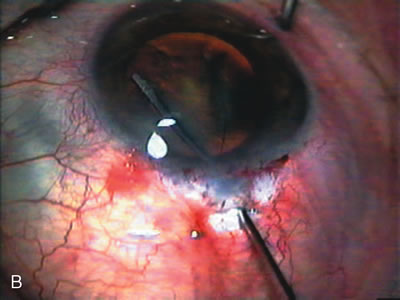

Fig. 7. Phacotrabeculectomy adjacent to a failed filter in cataractous eye. The ability to combine small-incision cataract extraction with trabeculectomy all through the same incision adjacent to the failed filter allows the surgeon to work in a familiar superior area. Avoiding incisions into the existing bleb decreases conjunctival buttonholes, hypotony, operating room time, and subconjunctival bleeding. A. Appearance of failed bleb with exposure of superior temporal quadrant gained with a corneal traction suture. B. Prepare a limbus-based conjunctival flap and a scleral flap. C. This bleb is at high risk to fail again justifying the need for MMC, 0.2 mg/cc applied on a pledget for 4 minutes. D. Insert the keratome and perform phacotrabeculectomy in the usual fashion.

The inflammation associated with lens extraction at any site usually causes complete failure of a marginal functioning bleb. In addition, pressure reduction by medical means is usually minimal in these recalcitrant cases, and combined surgery is indicated. In the past, these cases were approached with large-incision ECCE, clear corneal cataract incision, and bleb revision. Drawbacks included those mentioned earlier for large incision clear corneal cataract extraction, and bleb revision is often associated with conjunctival buttonholes, wound leaks, subconjunctival hematoma, destruction of friable sclera, and associated hypotony. With the advent of modern-day cataract surgery, a phacotrabeculectomy is often possible adjacent to the failed filter (Fig. 7). The ability to combine cataract extraction with implant and filtration surgery all through the same small incision has greatly improved outcomes for patients with marginal preoperative filters. There are several other viable options in this case. If the surgeon elects to remove the cataract through a temporal clear corneal incision, the bleb may be revised or a new adjacent filter fashioned. As mentioned earlier, revising a failed filter is technically challenging. If the surgeon believes it is not feasible to revise the filter or fashion a new one, a glaucoma drainage implant is a reasonable option combined with temporal lens extraction.172